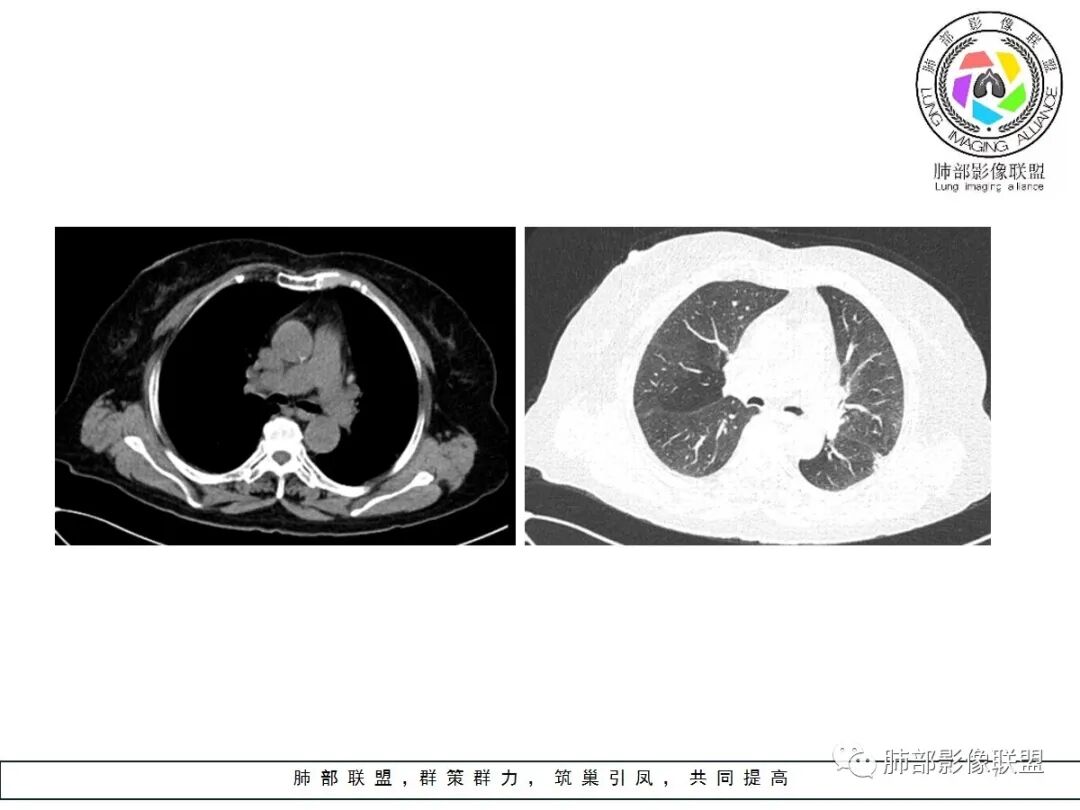

3.病灶显著强化不支持结核;边界清楚,肺门一侧波浪状改变,患者为老年女性,缺乏临床表现,尽管影像有一些炎性灶特点,但恶性肿瘤性病变不能除外。

二、早期结节型粘液腺癌诊断是腺癌诊断的难点之一,有哪些特点提示我们呢?根据曹悍波老师视频的总结如下:

1.中老年女性多见,单发,发病部位常位于双肺下叶胸膜下或叶间胸膜下,考虑与粘液重力分布有关。

2.50%左右为圆形,表现为椭圆形的结节生长方向与支气管垂直,其他的为不规则形,大部分病灶具有一定的恶性征象,少数不典型。

3.表现为混合磨玻璃结节,边界似清非清,为粘液向外飘散;实性结节收缩力弱,是由于粘液张力抵消了一部分纤维的收缩力,由于生长的不对称常导致收缩力不对称。

4.粘液腺癌的破坏力相对较低,血管及支气管破坏轻,可见血管造影征及空气支气管征;侵袭力弱,发展慢。

5.部分病灶需要与炎性病变、良性结节相鉴别,因此,临床抗炎治疗和短期随诊复查是非常必要的。